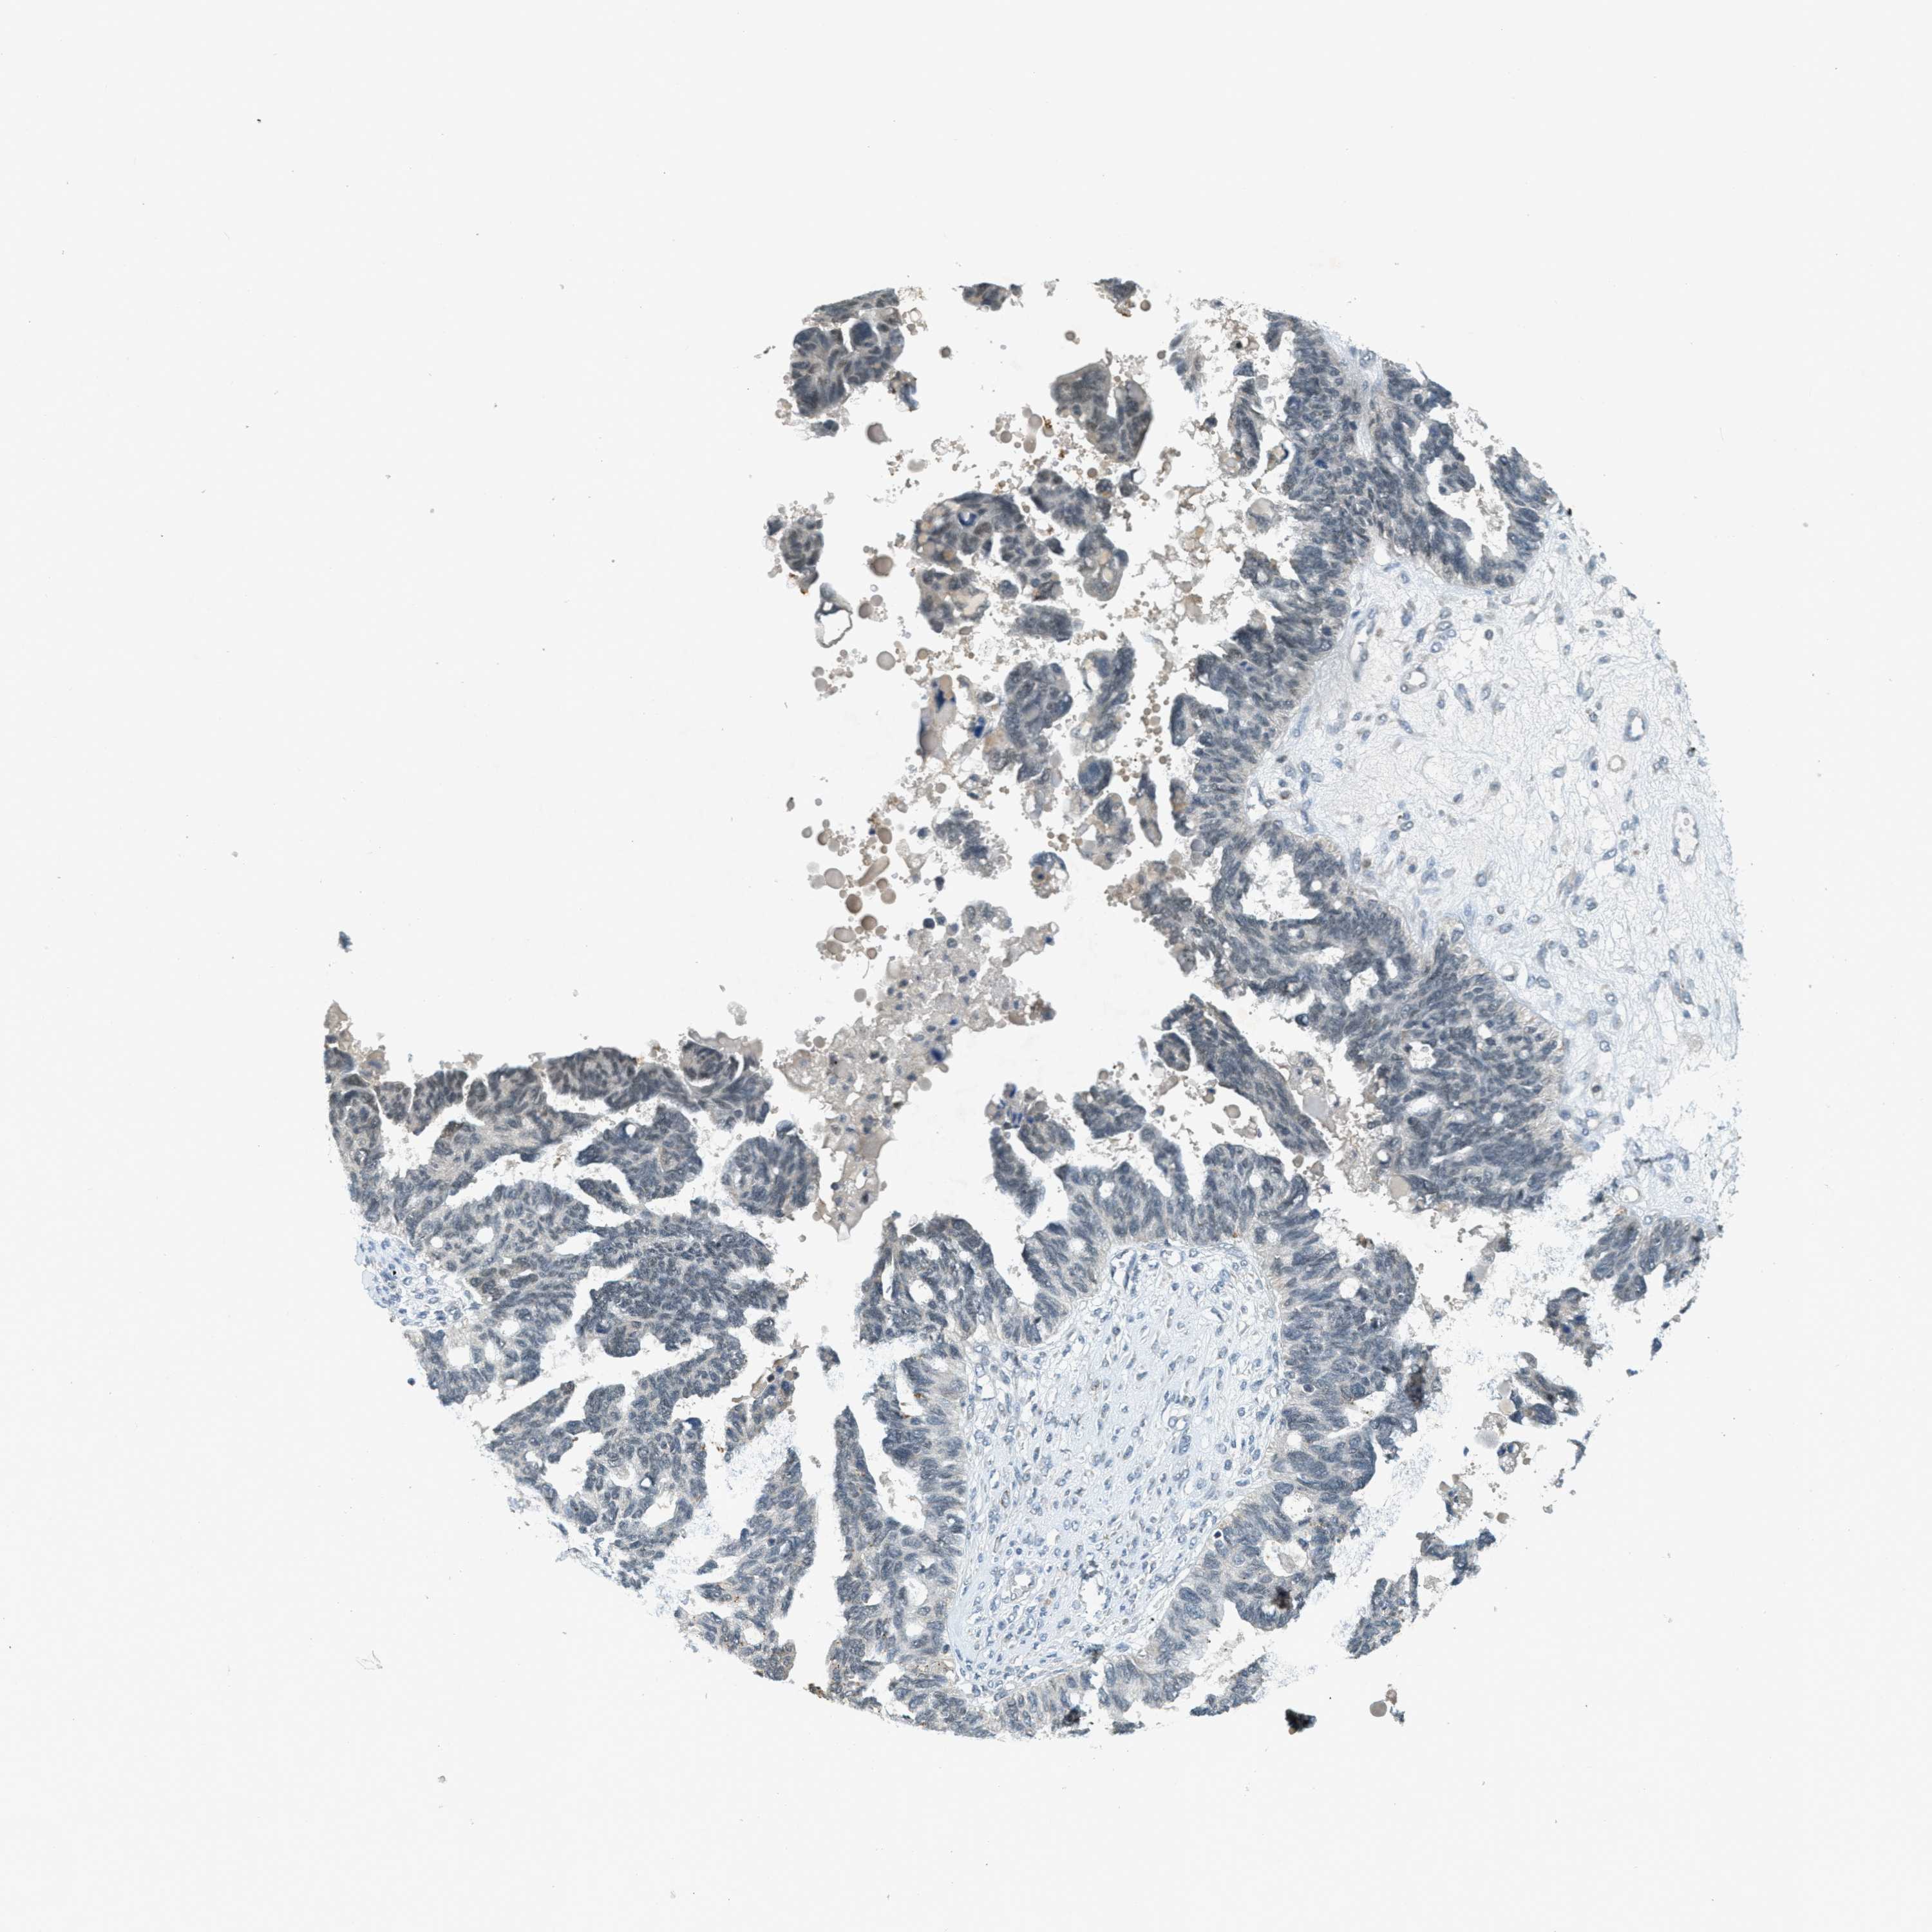

OVARIAN CANCER - Protein expressioni

A mouse-over function shows sample information and annotation data. Click on an image to view it in a full screen mode. Samples can be filtered based on level of antibody staining by selecting one or several of the following categories: high, medium, low and not detected. The assay and annotation is described here.

Note that samples used for immunohistochemistry by the Human Protein Atlas do not correspond to samples in the TCGA dataset.

Antibody stainingi

Antibody staining in the annotated cell types in the current human tissue is reported as not detected, low, medium, or high, based on conventional immunohistochemistry profiling in selected tissues. This score is based on the combination of the staining intensity and fraction of stained cells.

Each image is clickable and will lead to virtual microscopy that enables deeper exploration of all samples and also displays staining intensity scores, fraction scores and subcellular localization as well as patient and tissue information for each sample.

Antibody HPA036786

Antibody CAB017849

Staining

High

Medium

Low

Not detected

Intensity

Strong

Moderate

Weak

Negative

Quantity

>75%

75%-25%

<25%

None

Location

Nuclear

Cytoplasmic/membranous

Cytoplasmic/membranous,nuclear

Cystadenocarcinoma, serous, NOS

Carcinoma, endometroid

Cystadenocarcinoma, mucinous, NOS

Carcinoma, NOS